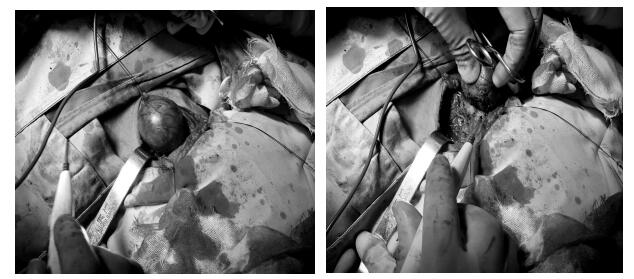

完善了所有术前检查后,肿瘤科主任张玉超组织主管医生牧永峥及肿瘤科外科组团队一起探讨该病人的病情及手术方案,在充分考虑了患者年龄较大、心肺功能较差、瘤体较大局部气管受压,轻度呼吸困难、麻醉耐受性低手术风险高等一系列问题,及时联系手麻科进行术前评估,最终制订好手术方案,积极完善好术前准备后,由张玉超主任主刀成功的为患者实施了“甲状腺左叶+峡部切除术” ,经过术中精细解剖,手术过程顺利,手术时长1小时,出血量仅约10mL。